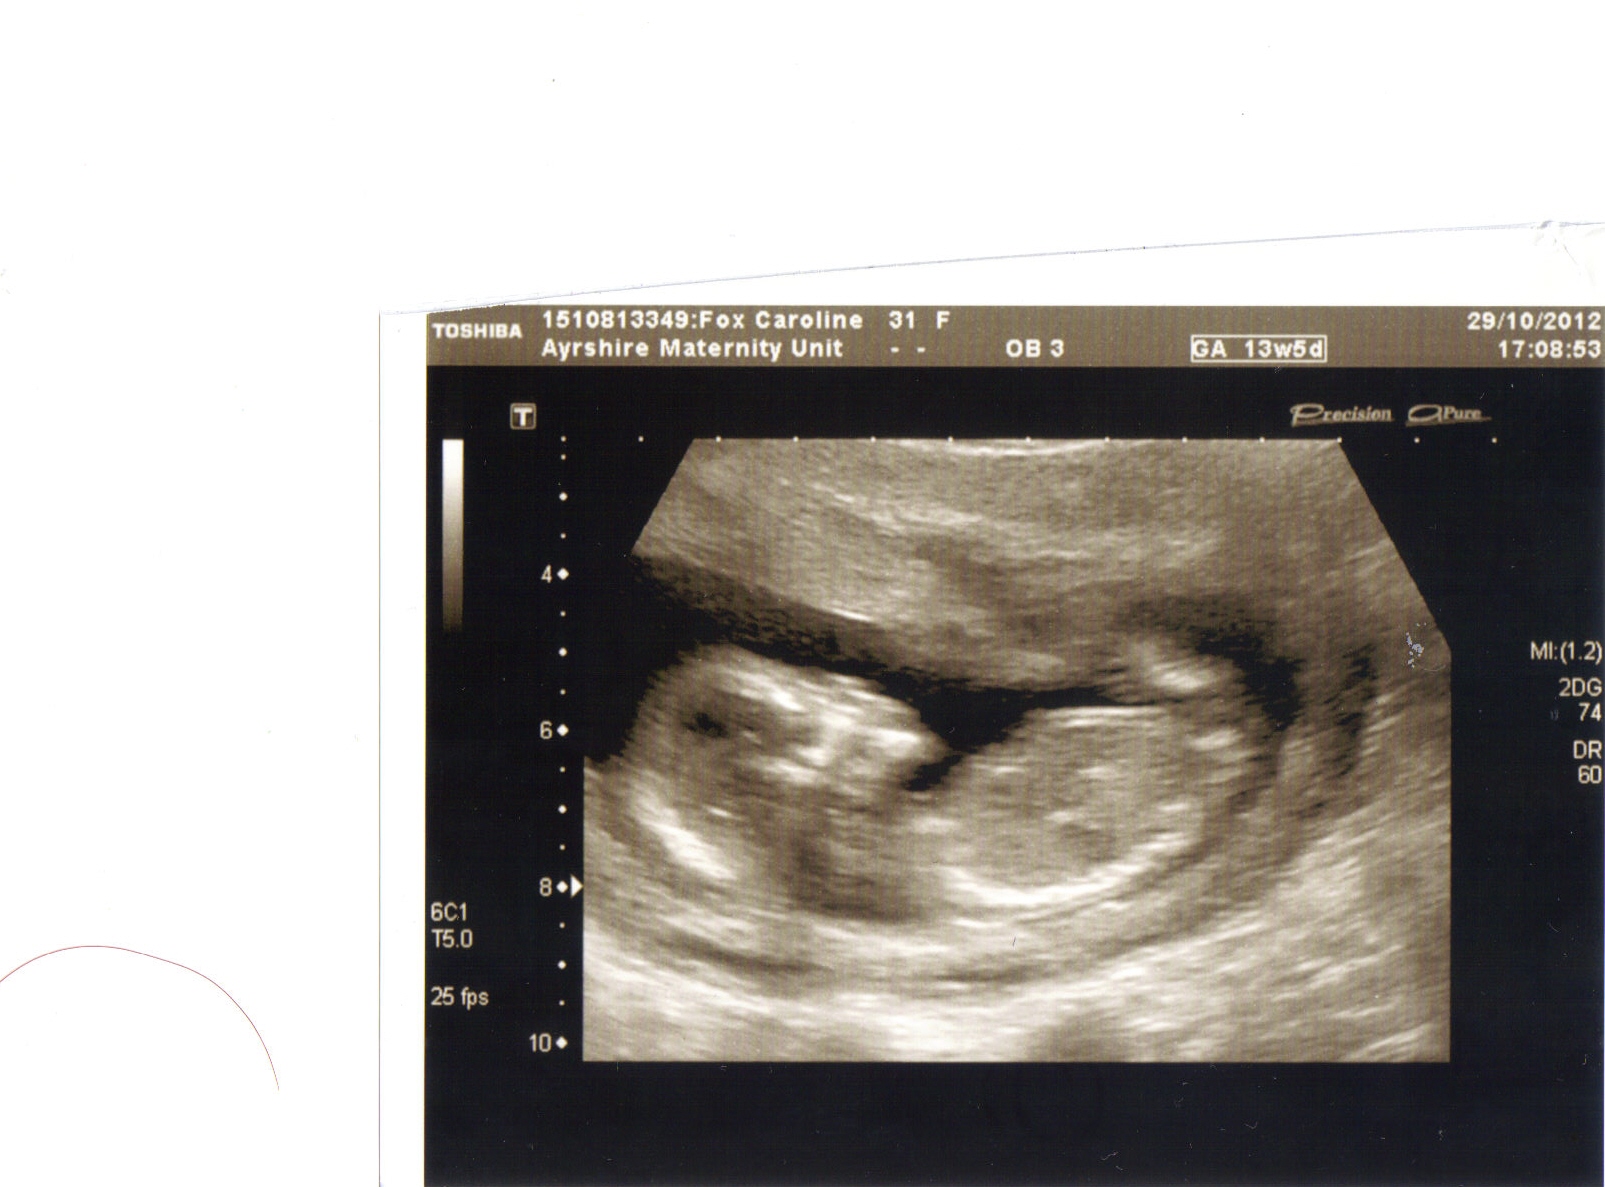

This scan was taken at 13+5 any guesses?